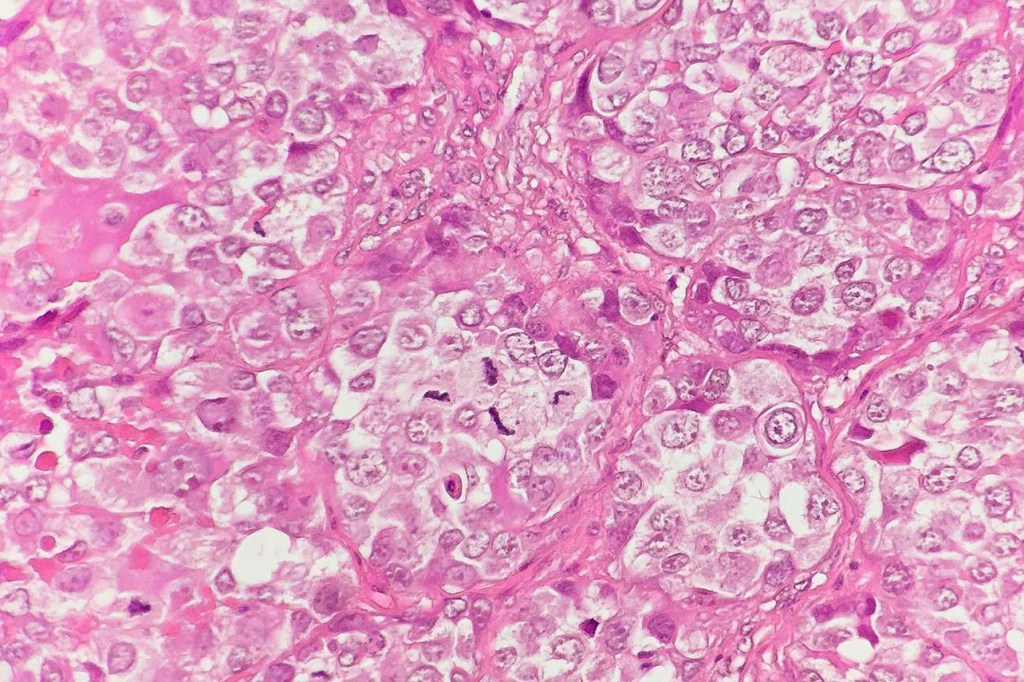

These are very rare variants of amelanotic or virtually amelanotic melanoma where a primary melanoma or a metastasis shows partial (DN) or complete loss (UN) of recognizable histological and immunohistochemical features. The histology may lead the pathologists to consider lymphoma, sarcoma, anaplastic carcinoma or a small cell tumor. Some examples of rhabdoid melanoma & melanoma with heterologous differentiation probably belong in this category. Ultimately, if there is no identifiable/recognizable primary tumor, diagnosis may only be comfortably made with next-generation sequencing. In the cases presented below, immunohistochemistry was of value in determining the melanoctic nature of the tumor (undifferentiated melanoma).